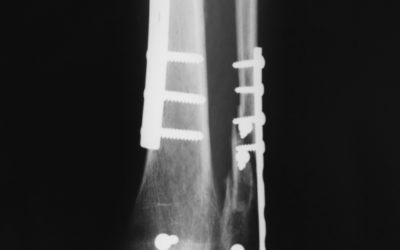

read moreTreating Ankle Fractures

Broken ankles can happen almost anywhere, anytime. A fracture might occur if you are in an accident, if you trip and fall, and even if you twist or roll your ankle. Thank goodness not all fractures require surgery!